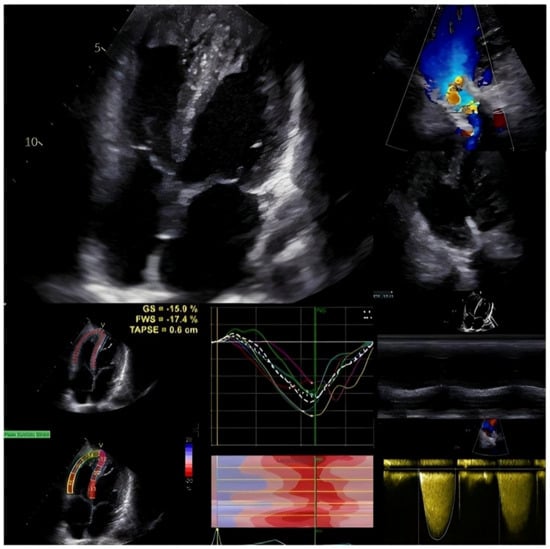

2.2. Post-Operative and Long-Term Evaluation

2.3. Advanced Echocardiography in Tetralogy of Fallot

2.4. New Perspectives in the Echocardiographic Assessment in Tetralogy of Fallot